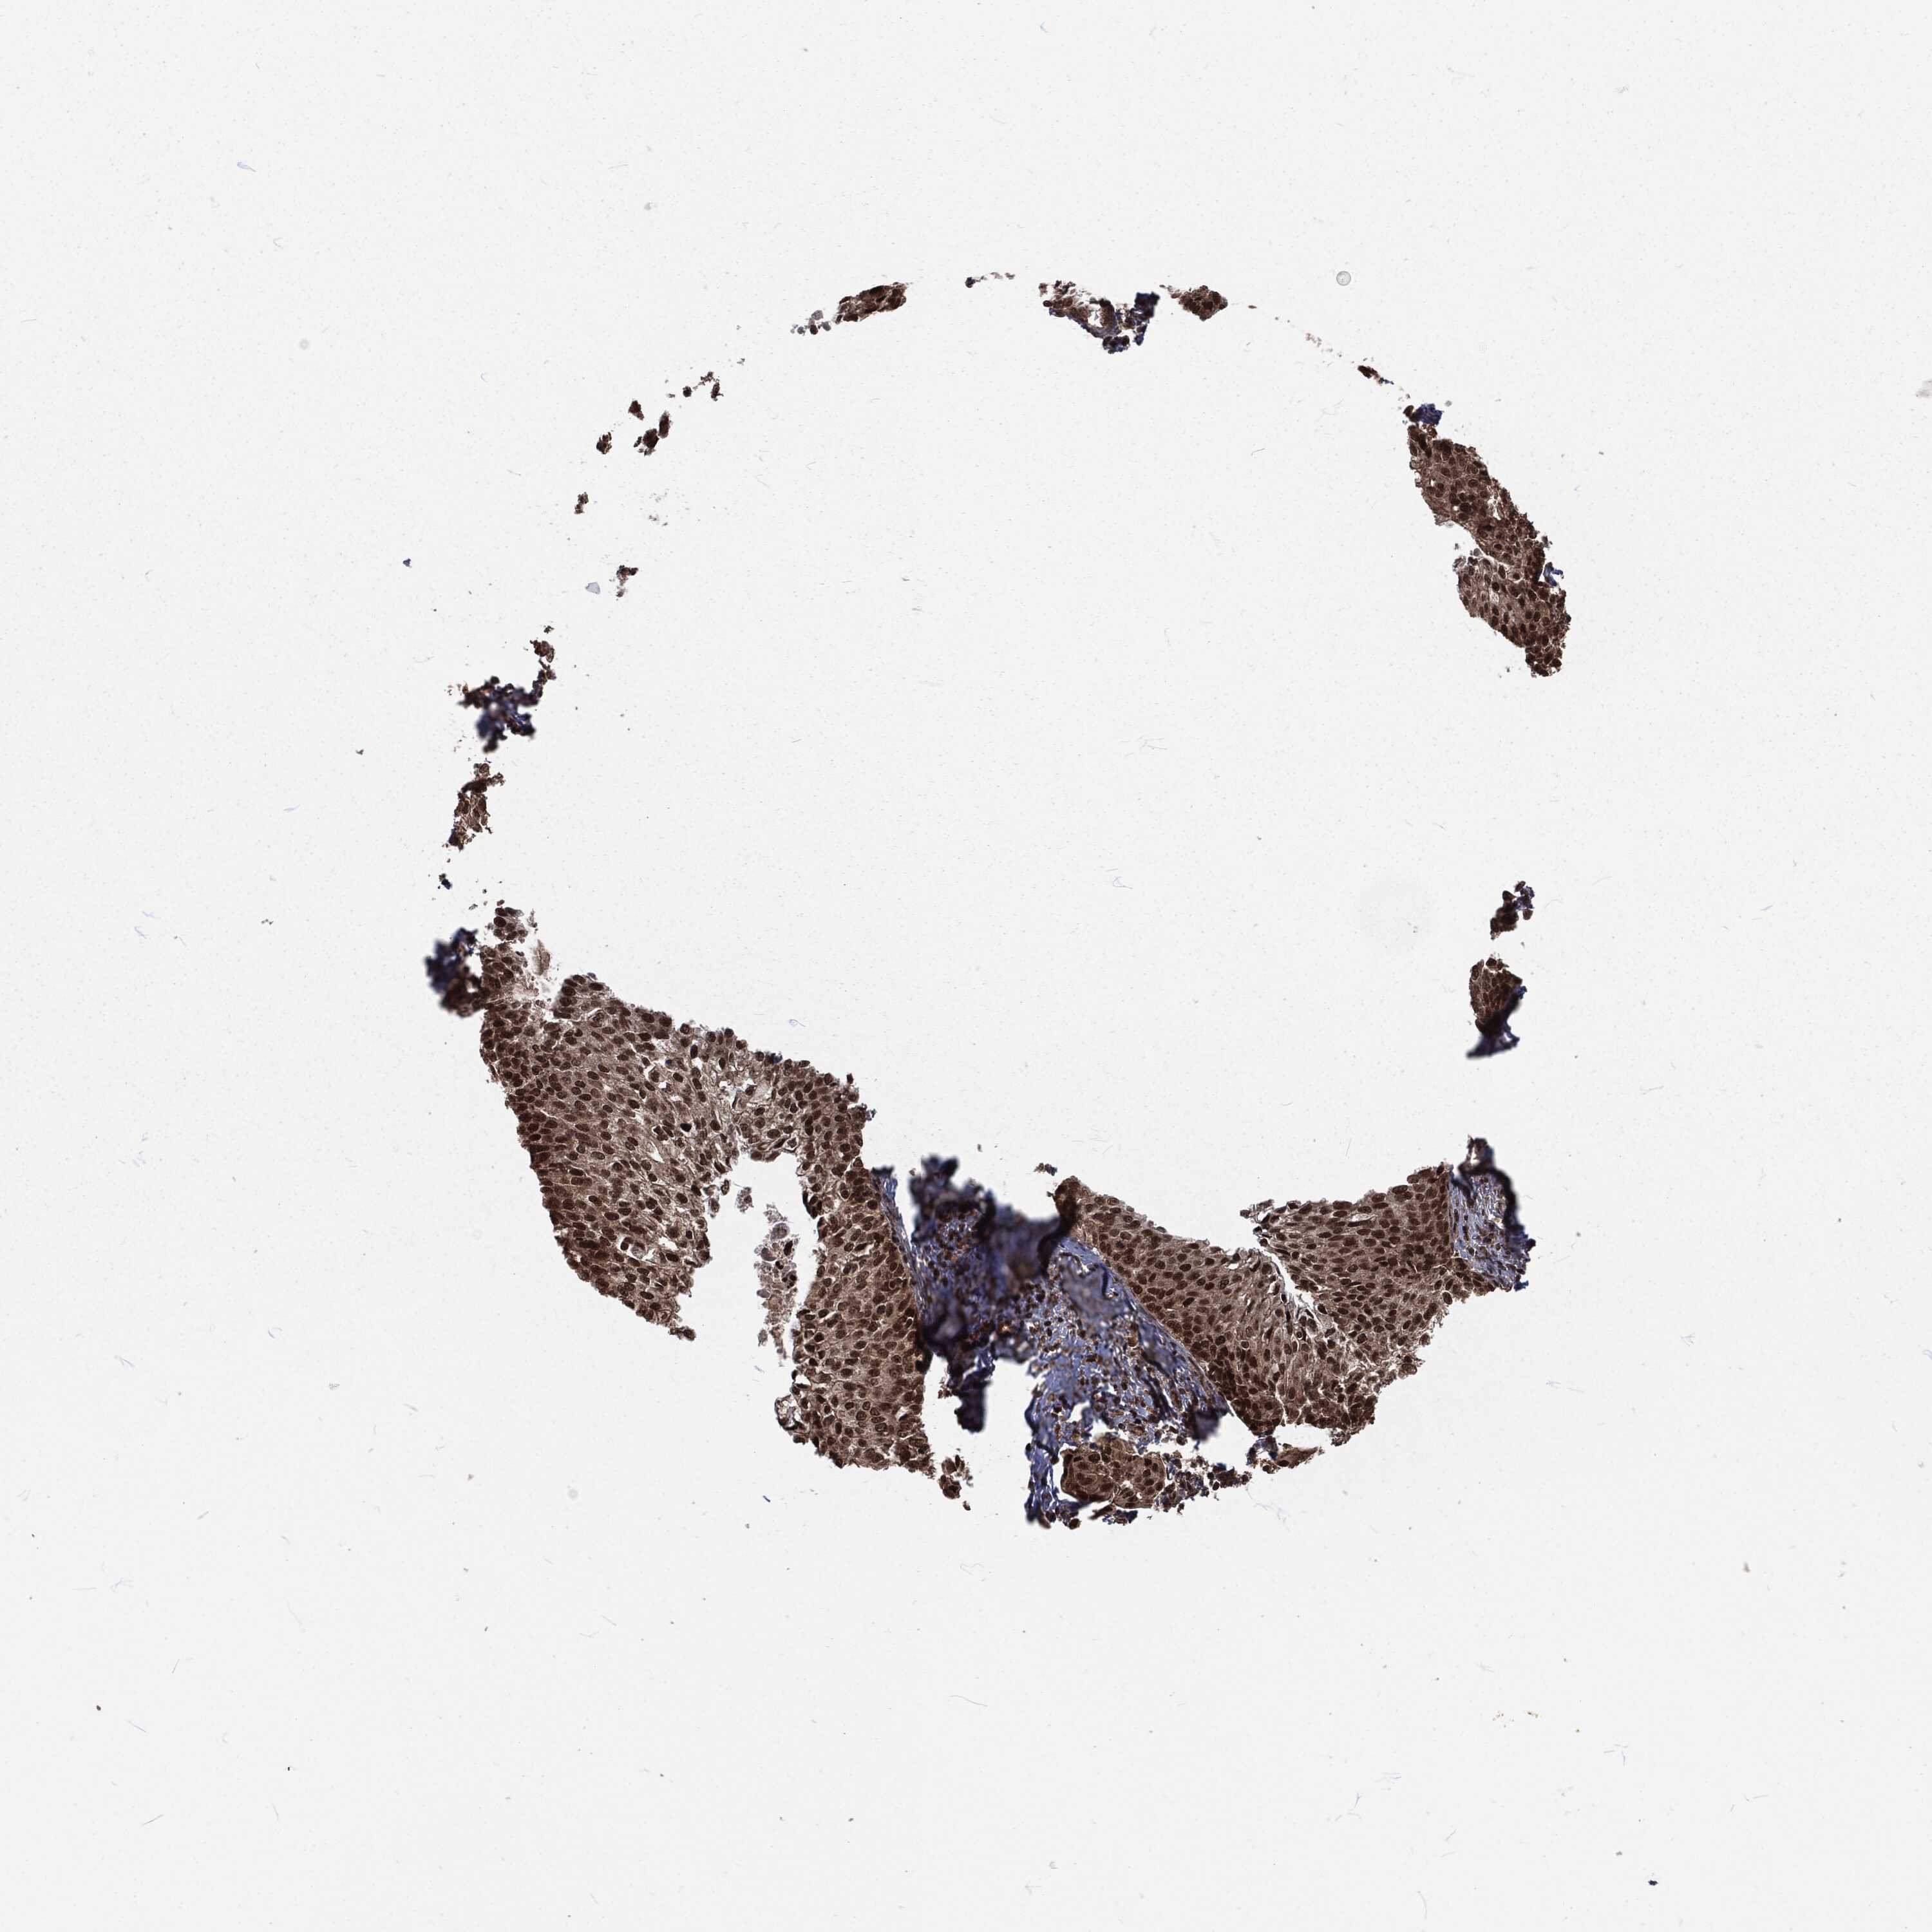

CERVICAL CANCER - Protein expressioni

A mouse-over function shows sample information and annotation data. Click on an image to view it in a full screen mode. Samples can be filtered based on level of antibody staining by selecting one or several of the following categories: high, medium, low and not detected. The assay and annotation is described here.

Note that samples used for immunohistochemistry by the Human Protein Atlas do not correspond to samples in the TCGA dataset.

Antibody stainingi

Antibody staining in the annotated cell types in the current human tissue is reported as not detected, low, medium, or high, based on conventional immunohistochemistry profiling in selected tissues. This score is based on the combination of the staining intensity and fraction of stained cells.

Each image is clickable and will lead to virtual microscopy that enables deeper exploration of all samples and also displays staining intensity scores, fraction scores and subcellular localization as well as patient and tissue information for each sample.

Antibody HPA041367

Antibody HPA076267

Staining

High

Medium

Low

Not detected

Intensity

Strong

Moderate

Weak

Negative

Quantity

>75%

75%-25%

<25%

None

Location

Nuclear

Cytoplasmic/membranous

Cytoplasmic/membranous,nuclear

Squamous cell carcinoma, NOS

Adenocarcinoma, NOS